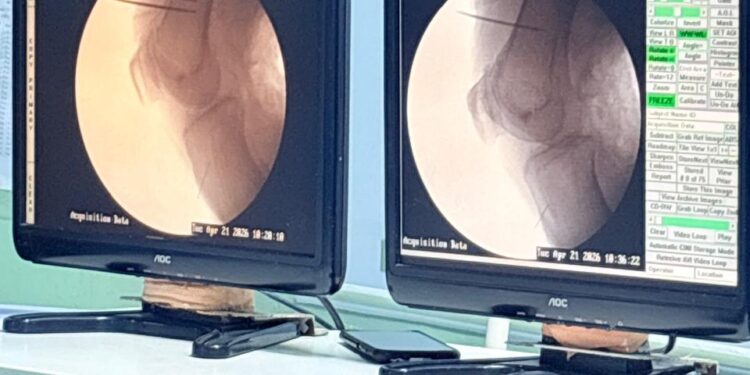

उत्तराखंड/ देहरादून में दर्द प्रबंधन के क्षेत्र में एक बड़ी उपलब्धि सामने आई है। यह उपलब्धि श्री महंत इन्दिरेश अस्पताल के नाम दर्ज हुई है। श्री महंत इन्दिरेश अस्पताल में पहली बार कूल्ड रेडियोफ्रीक्वेंसी एब्लेशन (आरएफए) तकनीक के माध्यम से घुटनों के गंभीर दर्द का सफल उपचार किया गया। इस आधुनिक और कम हस्तक्षेप वाली प्रक्रिया से बिना सर्जरी मरीज को लंबे समय तक राहत मिली है। 64 वर्षीय सावित्री देवी, जो लंबे समय से घुटने की ग्रेड-4 ऑस्टियोआर्थराइटिस से पीड़ित थीं और अत्यधिक दर्द के कारण चलने-फिरने में असमर्थ हो गई थीं, उन्हें दवाइयों और पारंपरिक उपचारों से कोई लाभ नहीं मिल रहा था। ऐसे में डॉक्टरों ने बिना ऑपरेशन के विकल्प के रूप में कूल्ड आरएफए प्रक्रिया अपनाई, जिसमें विशेष सुई के जरिए घुटनों की दर्द उत्पन्न करने वाली जेनिक्यूलर नसों को नियंत्रित किया जाता है, जिससे दर्द के संकेत दिमाग तक कम पहुंचते हैं और मरीज को लंबे समय तक राहत मिलती है।

प्रक्रिया के बाद सावित्री देवी को दर्द से काफी राहत मिली और अब वे पहले की तुलना में बेहतर तरीके से चल-फिर पा रही हैं, जिससे उनकी जीवन गुणवत्ता में स्पष्ट सुधार हुआ है। इस तकनीक की खासियत यह है कि इसमें न तो सर्जरी की जरूरत होती है और न ही कोई बड़ा चीरा लगाया जाता है, साथ ही मरीज को उसी दिन अस्पताल से छुट्टी मिल जाती है। कम खर्च, सीजीएचएस कैशलेस सुविधा और जल्दी रिकवरी के कारण यह प्रक्रिया बुजुर्ग और हाई-रिस्क मरीजों के लिए सुरक्षित और प्रभावी विकल्प साबित हो रही है। विशेषज्ञों के अनुसार, अब तक यह सुविधा देश के चुनिंदा महानगरों और उन्नत पेन मैनेजमेंट केंद्रों तक सीमित थी, लेकिन देहरादून में इसकी शुरुआत से उत्तराखंड के मरीजों को अपने ही शहर में अत्याधुनिक उपचार उपलब्ध हो सकेगा।